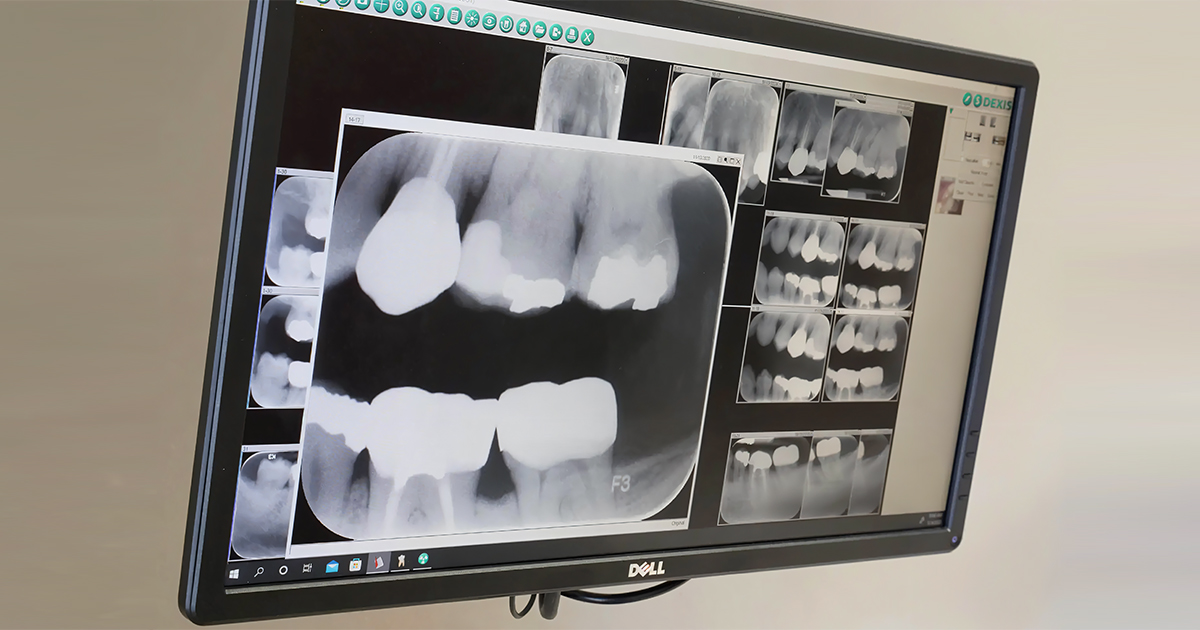

The quality of images produced by traditional x-rays is often quite poor. The contrast between light and dark areas is not very good, making it difficult to diagnose initial abnormalities on the x-ray film. The image must be reviewed only in its original size, as seen on the film.

In contrast, digital radiography produces high-quality images with better contrast. These images can be zoomed in for further observation and easily adjusted for brightness and contrast using the software. This flexibility helps enable more accurate diagnoses and effective treatment planning.

But with digital X-rays, all these problems are reduced to nil, as all the data for a patient can easily be stored in a cloud-based file, which contains the data regarding the tooth number, date, and time against the patient that is captured. The data quality also remains the same and does not degrade over the years and is safely backed up to refer to anytime. This saved data can even be used for legal documentation and medico-legal accountability, ensuring that every radiograph can be traced, retrieved, and defended with clarity. This hardly takes 1–2 minutes to sort or find if needed in subsequent appointments.

Additionally, these images can be easily transferred or shared amongst fellow dentists for further consultation and discussions or can even be shared with the patients if they want one, easily in just minutes. The space required is thus reduced from physical space to digital space of just KB or MB.

As discussed, cloud storage makes it easier to circulate images. With new technologies, AI-based solutions, and specific software that come with digital setups, it is even easier for dental professionals to do so. The Waldent RTA Intelli-Sensor RVG by Woodpecker has its own software that helps dentists easily circulate x-rays. Their software is easy to use and makes the x-ray management for each patient simpler. It provides a user-friendly interface for acquiring, viewing, and managing images.